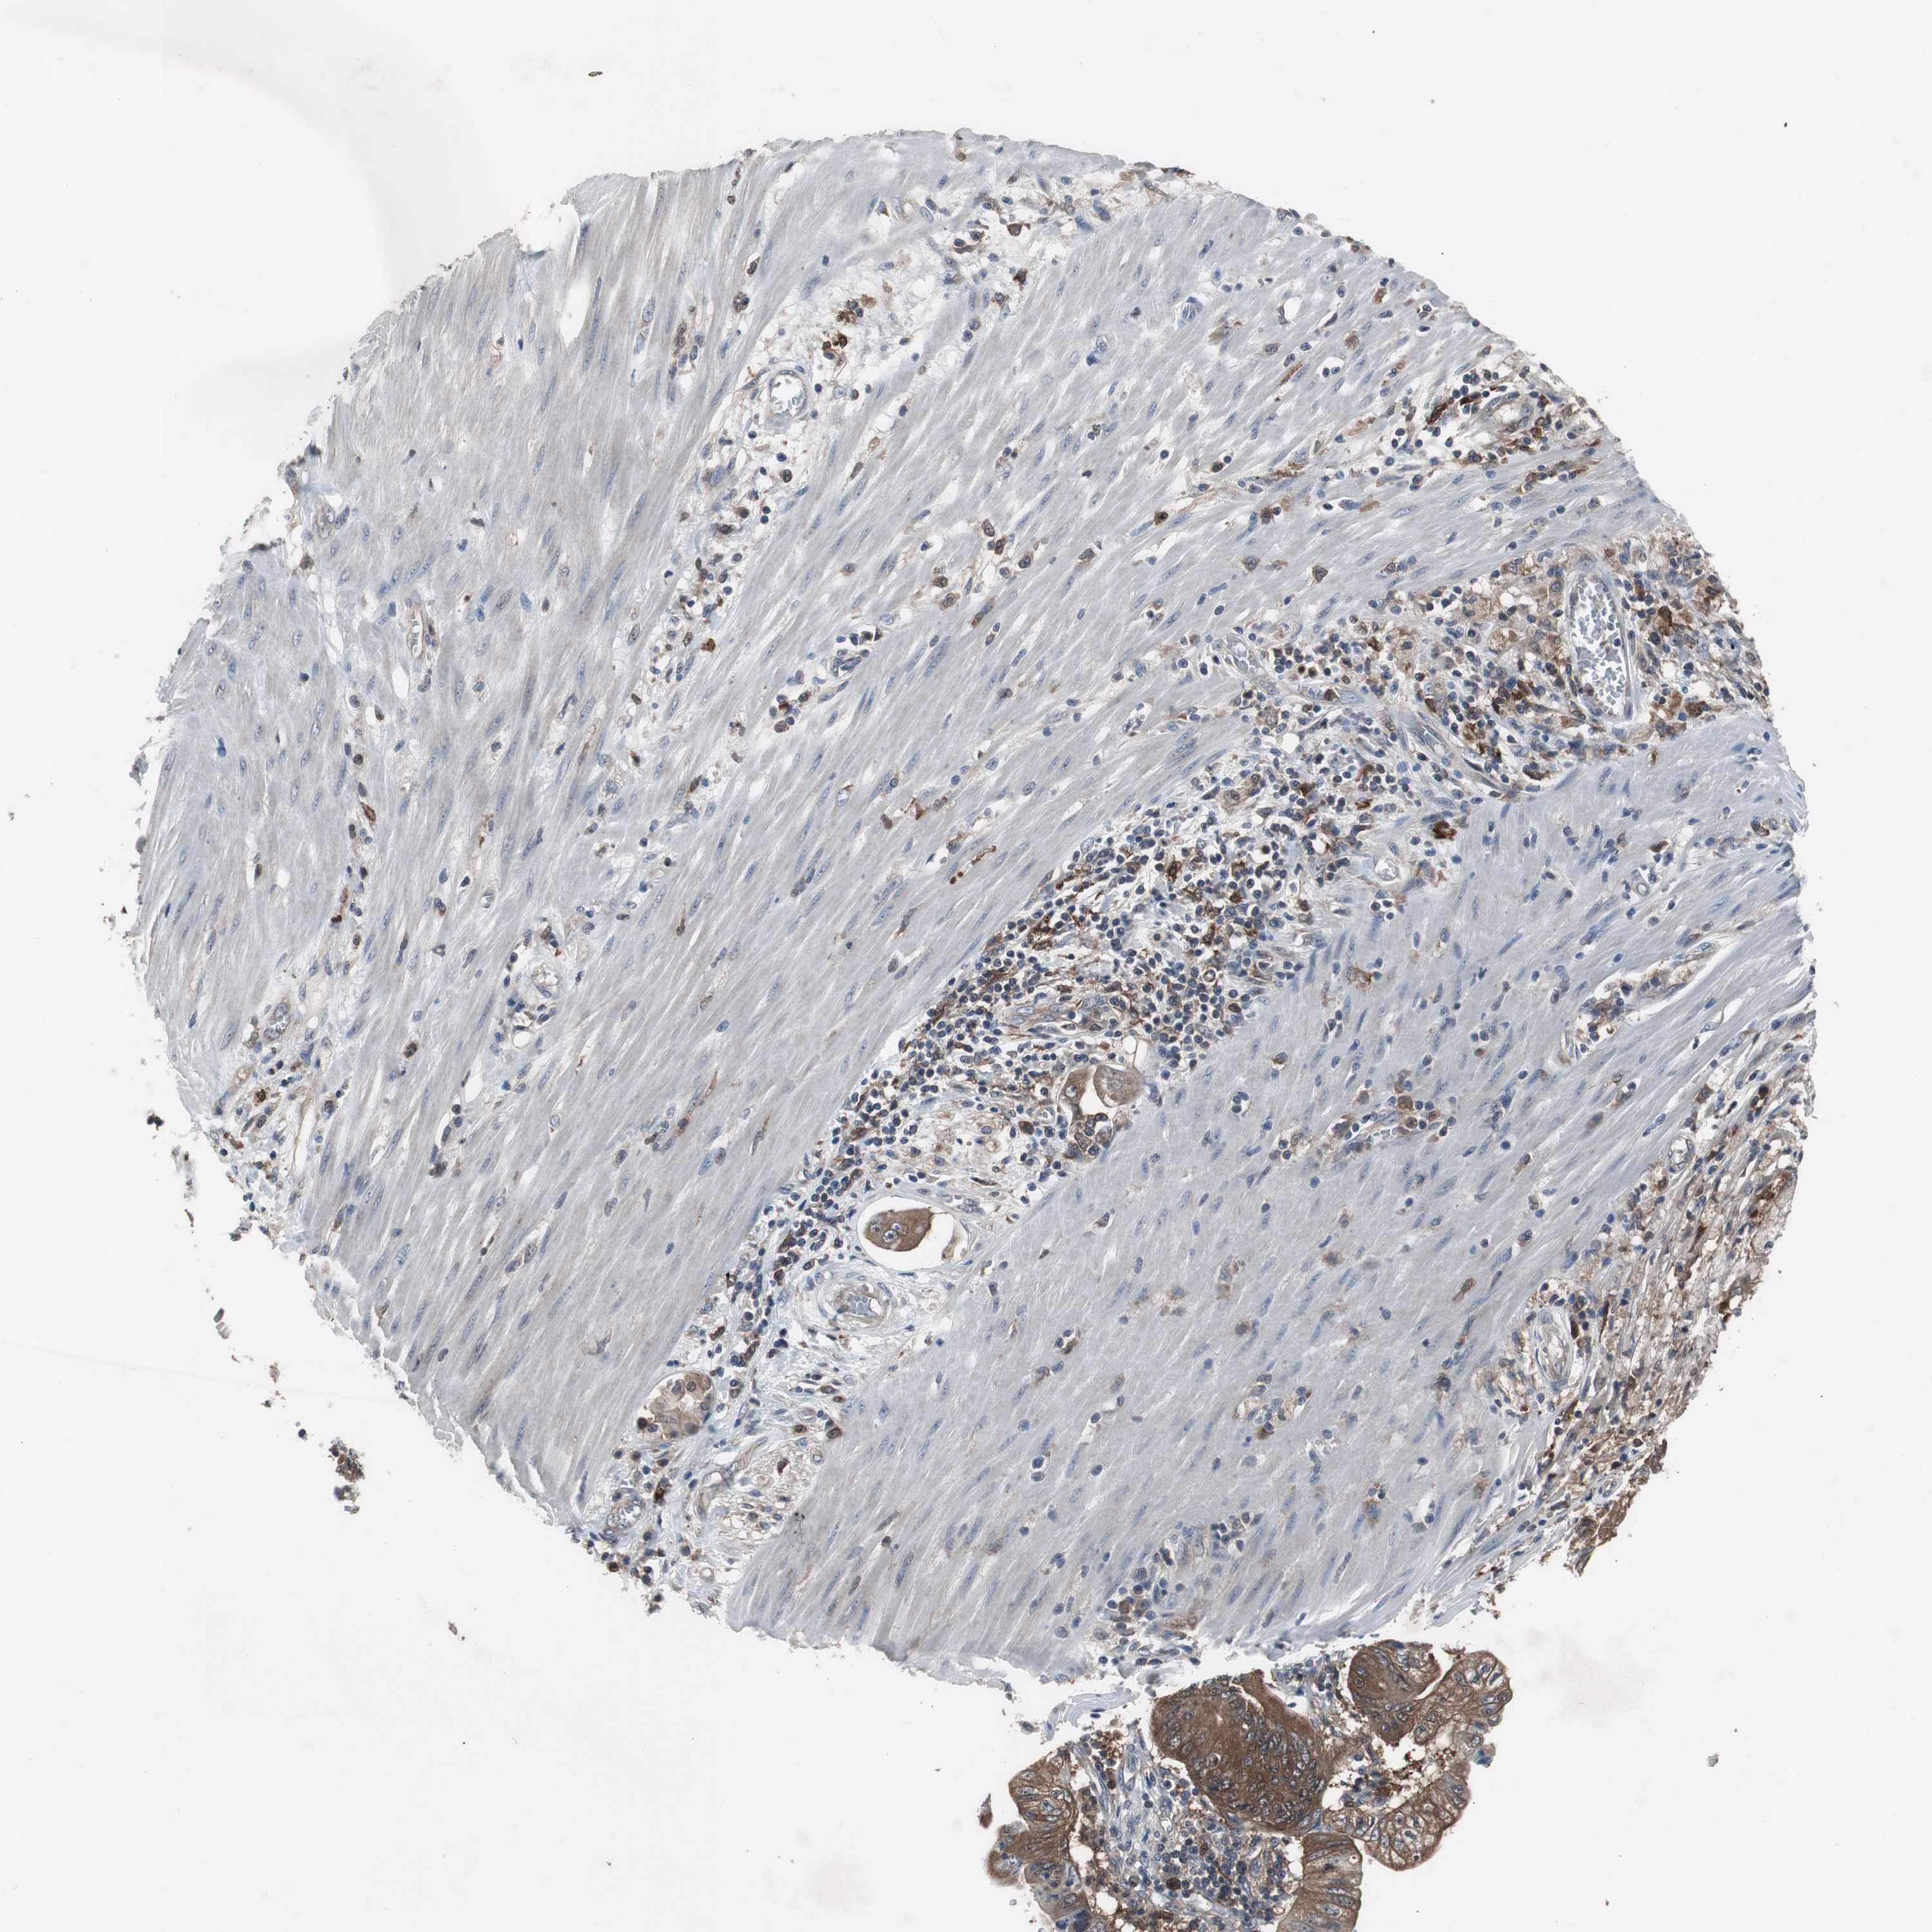

PANCREATIC CANCER - Protein expressioni

A mouse-over function shows sample information and annotation data. Click on an image to view it in a full screen mode. Samples can be filtered based on level of antibody staining by selecting one or several of the following categories: high, medium, low and not detected. The assay and annotation is described here.

Note that samples used for immunohistochemistry by the Human Protein Atlas do not correspond to samples in the TCGA dataset.

Antibody stainingi

Antibody staining in the annotated cell types in the current human tissue is reported as not detected, low, medium, or high, based on conventional immunohistochemistry profiling in selected tissues. This score is based on the combination of the staining intensity and fraction of stained cells.

Each image is clickable and will lead to virtual microscopy that enables deeper exploration of all samples and also displays staining intensity scores, fraction scores and subcellular localization as well as patient and tissue information for each sample.

Antibody HPA003565

Antibody CAB005312

Staining

High

Medium

Low

Not detected

Intensity

Strong

Moderate

Weak

Negative

Quantity

>75%

75%-25%

<25%

None

Location

Nuclear

Cytoplasmic/membranous

Cytoplasmic/membranous,nuclear

Adenocarcinoma, NOS

Adenocarcinoma, metastatic, NOS